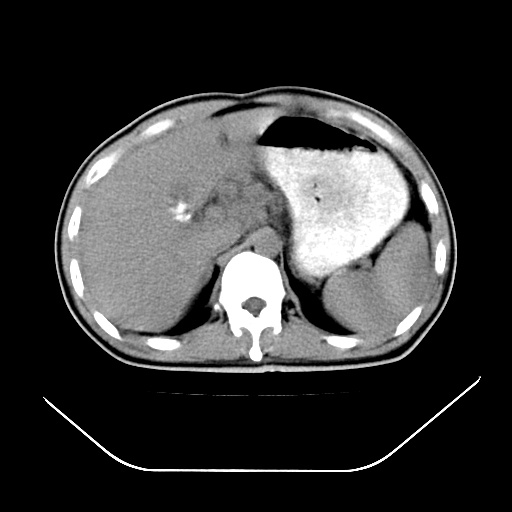

以下是引用深泽交通医院在2008-7-17 12:05:00的发言:[br]肝门淋巴结肿大;胆结石

以下是引用文莱在2008-7-17 16:32:00的发言:[br]胆囊结石 余未见异常

以下是引用随光逐影在2008-7-17 17:52:00的发言:[br]1)胆囊结石。2)肝门及胰头区淋巴结肿大可能(原因不明);建议行进一步检查。

以下是引用卜一在2008-7-17 16:37:00的发言:[br]支持胆囊结石!!!至于胰头区病变——建议强化后再定论!